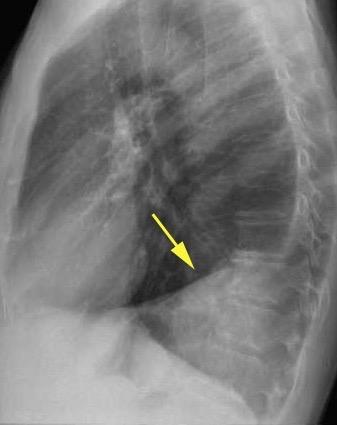

Tromboembolismo pulmonar Diafragma elevado 20%

Atelectasia crónica de LLI en paciente con enfermedad neuromuscular.